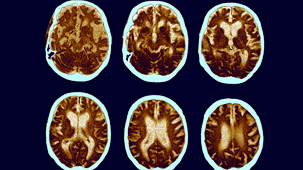

Thanks to the introduction of a range of non-invasive brain imaging techniques, neurosurgical procedures in particular have been revolutionised.

Electroencephalography, Functional Magnetic Resonance Imaging and other machines have increased our knowledge of the brain's inner workings.

Functional Magnetic Resonance Imaging (FMRI) and magnetoencephalography (MEG) have become essential tools for investigating the brain. Thanks to brain scanning, our knowledge of core physical processes - memory, sight, muscle control - has been hugely improved. But are researchers justified in using these tools to delve into more complex and subjective areas such as emotions, aesthetics and morality? (2009)

Dr Mark Lythgoe investigates the technology of brain scanning. Will this technique ever help people suffering from mental illnesses such as depression and schizophrenia? (2007)

Alzheimer's disease is the most common form of dementia. Damaged tissue builds up in the brain and forms deposits called 'plaques' and 'tangles' which cause the cells around them to die. It also affects chemicals in the brain which transmit messages from one cell to another.

The most common type of dementia occurs when brain tissue degeneration causes a progressive deterioration in mental function and ability. It's more likely to develop as people get older, but can affect younger people too. (2011)